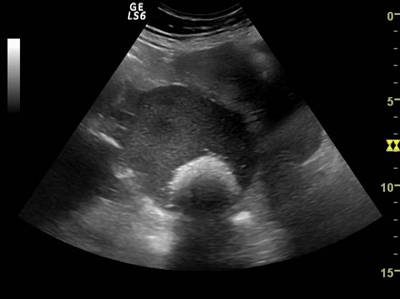

Fig. nr. 399.Chist ovarian anecogen unilocular , situat deasupra vezicii urinare si corpului uterin, la ecografia abdominala